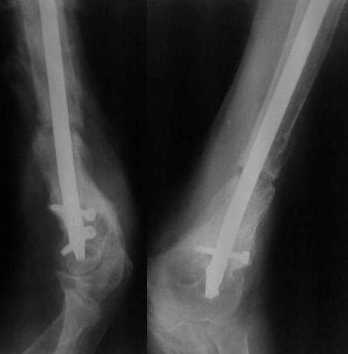

Более года назад пациент был оперирован в одном из НИИТО. При контрольном осмотре через год: болевой синдром, контрактура в локтевом суставе, патолгическая подвижность нижней трети плеча